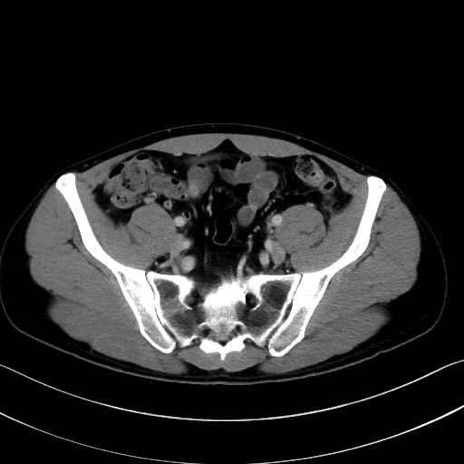

腸骨筋 (Iliacus)

肛門挙筋 (Levator ani)

大殿筋 (Gluteus maximus)

中殿筋 (Gluteus medius)

小殿筋 (Gluteus minimus)